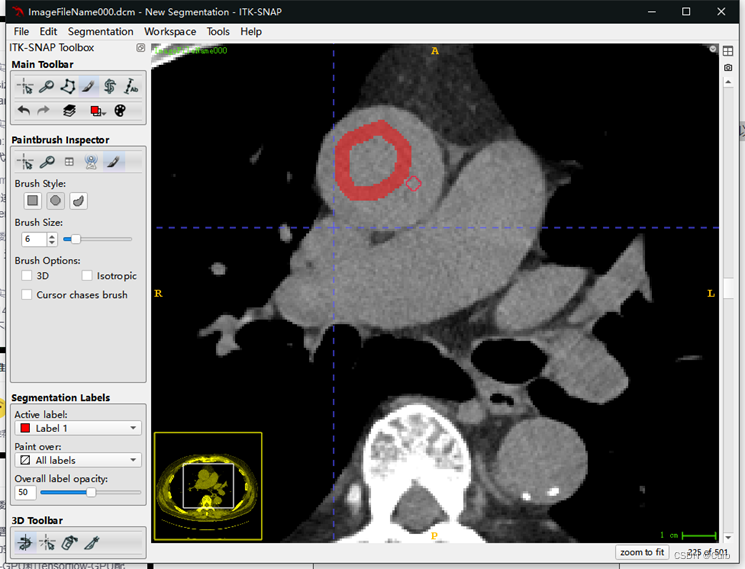

标注方法二:画笔标注

这里只进行简单介绍,流程和上面的套索标注差不多

在这一功能中可以使用类似画笔工具对标注的mask进行修改,在这个功能下鼠标左键是画笔,鼠标右键是橡皮。可以通过brush style和brush size调整笔头的形状和大小。